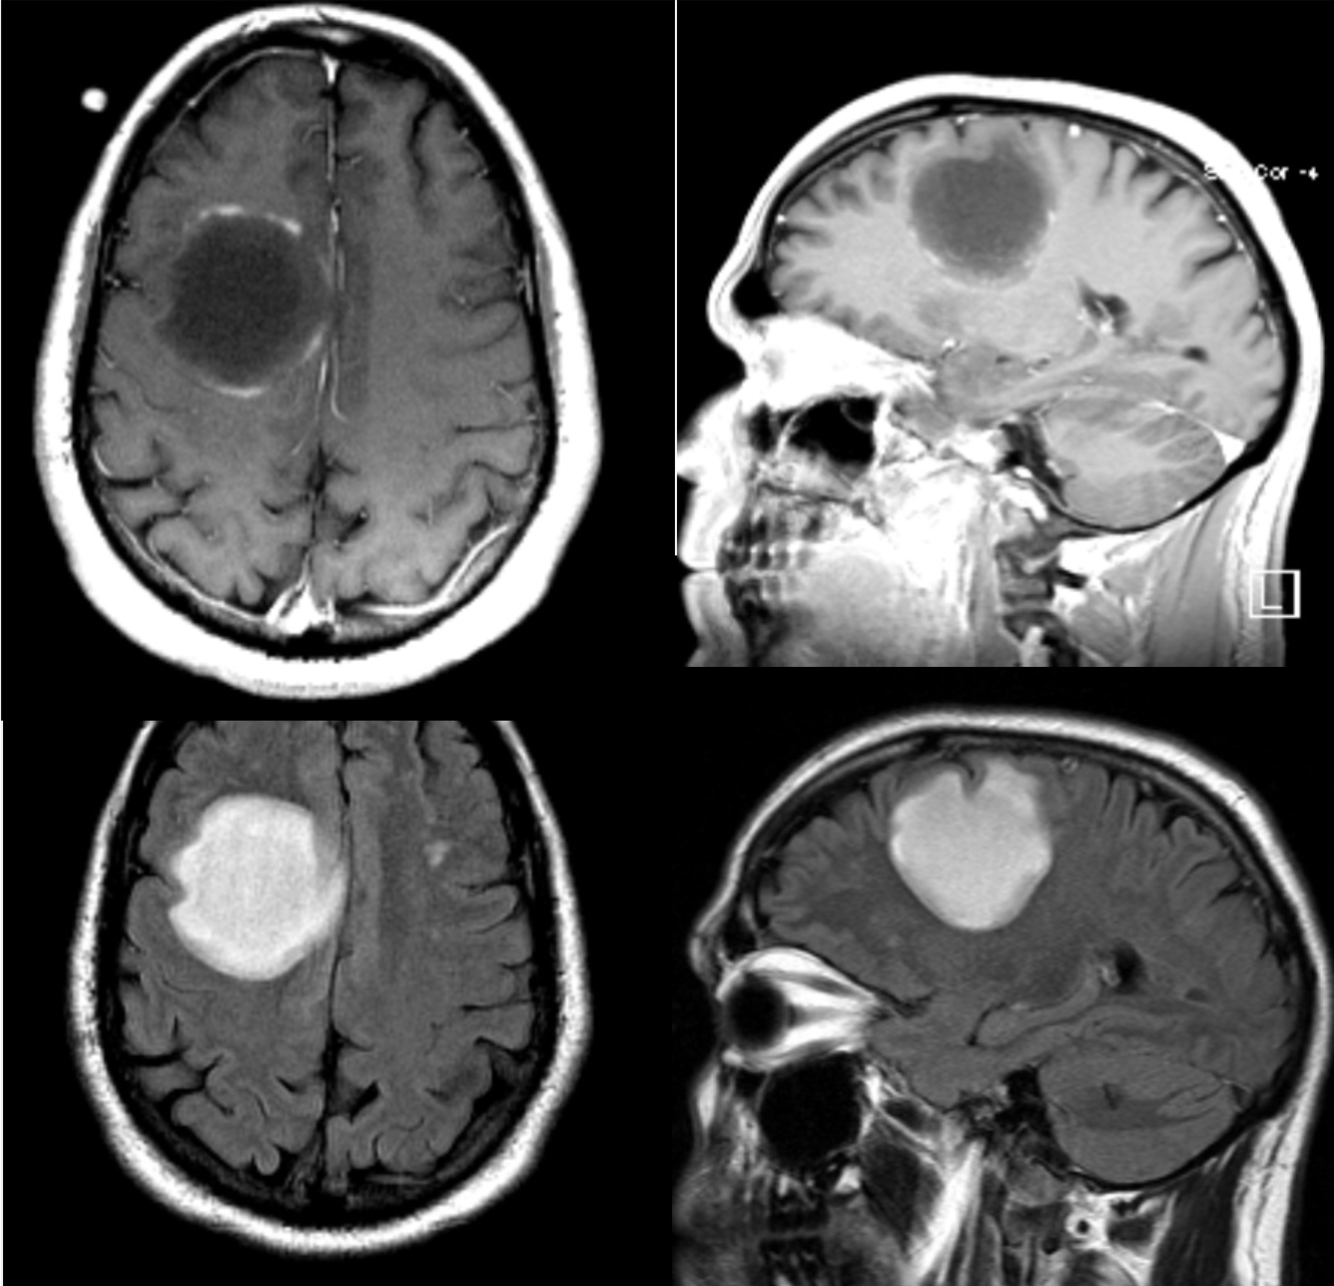

A 50 year-old man developed personality changes and subtle left-sided weakness.

Multiple sclersois - Tumefactive lesion